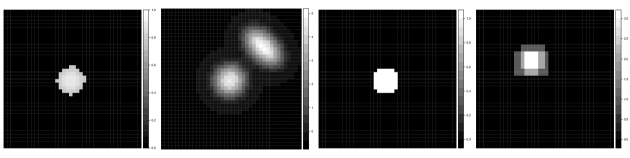

Here we are interested in recovering a target structure in a two-dimensional image using atlases. We simulate a 40 40 grid, displayed in Figure 2. Suppose that each of the atlas segmentations perform well, each being only slightly offset from the truth. The atlases are also displayed in Figure 2.

To compare results of our procedure with and without covariates, we find the signed distance label (SDL) transforms for each atlas (Iglesias et al., 2012). An SDL transform for a binary image assigns to each pixel a number corresponding to its distance from the nearest edge in an image, where an edge is indicated by a zero adjacent to a one. The sign of the distance corresponds to whether or not the pixel is inside or outside an identified structure; e.g., a pixel has negative distance if it is inside the structure, positive distance if it is outside, and zero if it is on the boundary. We consider the sum of the signed distance label transform maps as a possible covariate. In this case, the dimension of the predictor space with and without the covariate included is and , respectively. In the former case, our CMP prior is induced by supposing a priori that a voxel with a large negative signed distance label has probability 0.9 of being in the structure, and probability 0.10 if its signed distance label is large positive. With no predictors at all, we induce the prior on by supposing there is a 50% chance that a borderline voxel (signed distance label = 0) is truly part of the structure. Further discussion of prior elicitation for the numerical experiments, as well as MCMC implementation, is in the online Supplementary Material.

Figure 3 displays the posterior probability maps obtained from including the signed distance labels as covariates as well as the results from using an intercept-only model. We observe a more clearly-defined region of high and low probability when the covariate information is included, whereas using no covariate information results in a less clearly defined region. The latter is a byproduct of the fact than an intercept-only Bayesian probit regression is equivalent to allowing every pixel equal prior probability of inclusion in the structure, so that the atlases alone determine the likely region(s) of interest.